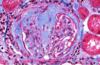

What is seen here?

• cells responsible?

crescentic glomerulonephritis - involves Bowman’s space

proliferating partietal epithelial cells and inflitrating macrophages cause this